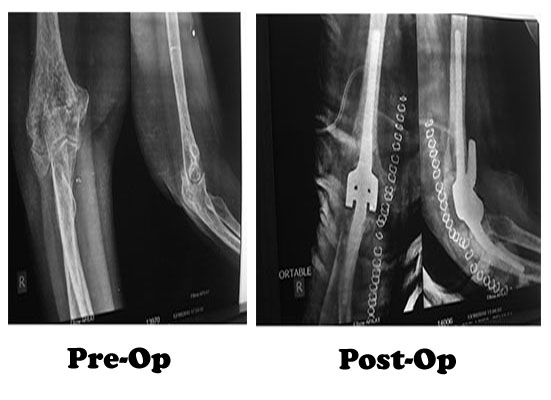

A severe fracture of one or more bones that make up the elbow is another common reason people have elbow replacements. If the elbow is shattered, it may be very difficult for a doctor to put the pieces of bone back in place. In addition, the blood supply to the bone pieces can be interrupted. In this type of case, a surgeon may recommend an elbow replacement. Older patients with osteoporosis (fragile bone) are most at risk for severe elbow fractures. In addition, some fractures do not heal well and may require an elbow replacement to address continuing probably.

To reach the elbow joint, your surgeon will make an incision (cut), usually at the back of the elbow. After making the incision, your surgeon will gently move muscles aside to get access to the bone. After removing scar tissue and spurs around the joint, your surgeon will prepare the humerus to fit the metallic piece that will replace that side of the joint. The same preparation is done for the ulna.The replacement stems are placed into the humerus and ulna bones, and kept in place with a bone cement. The two stems are connected by a hinge pin. After the wound is closed, a padded dressing is then placed to protect the incision while it heals. Some surgeons will place a temporary tube in the joint to drain the surgical fluid. This tube can be easily removed in your hospital room within the first few days after surgery.